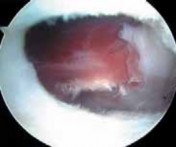

Failure to fully release tendon ■ The iliopsoas tendon forms from the psoas and iliacus muscles. The tendon sometimes

may remain bifid all the way to its insertion on the lesser trochanter. Whether addressing the tendon from the peripheral compartment (

FIG 4A–G

) or from its insertion within the iliopsoas bursa (

FIG 4H,I

), if the tendon looks inordinately small, search for a separate portion of the tendon. Failure to fully release the tendon fibers may result in incomplete resolution of the snapping.

TECHNIQUES A B C D E F G H I ### FIG 4 • A–G. The iliopsoas tendon of the right hip is exposed from the peripheral compartment. A. The initial tendon viewed through a capsular window is fully identified, but is abnormally small. B. This tendon is released with a basket. C. A stump remains. D. This is resected with a shaver. E. Further dissection exposes a more substantial portion of the iliopsoas tendon. F. This is released as well. G. Complete release of the bifid tendon is documented. H,I. Viewing the iliopsoas tendon of a right hip at its insertion on the lesser trochanter within the iliopsoas bursa. H. A bifid iliopsoas tendon is identified with medial (

) and lateral () bands separated by a vessel (

two white asterisks

) coursing perpendicular. I. The lateral band (

black asterisks

) has been released with a flexible RF device, revealing the medial band (

white asterisk

) which subsequently is released. (Courtesy of J. W. Thomas Byrd, MD.)**